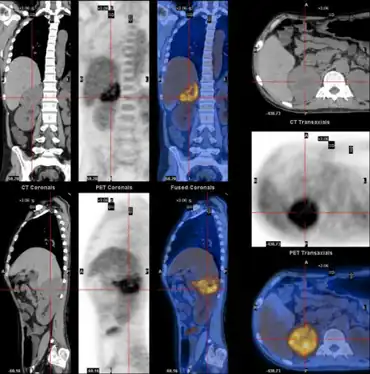

| WDHA caused by pheochromocytoma-,PET-CT scan demonstrating well defined adrenal mass | |